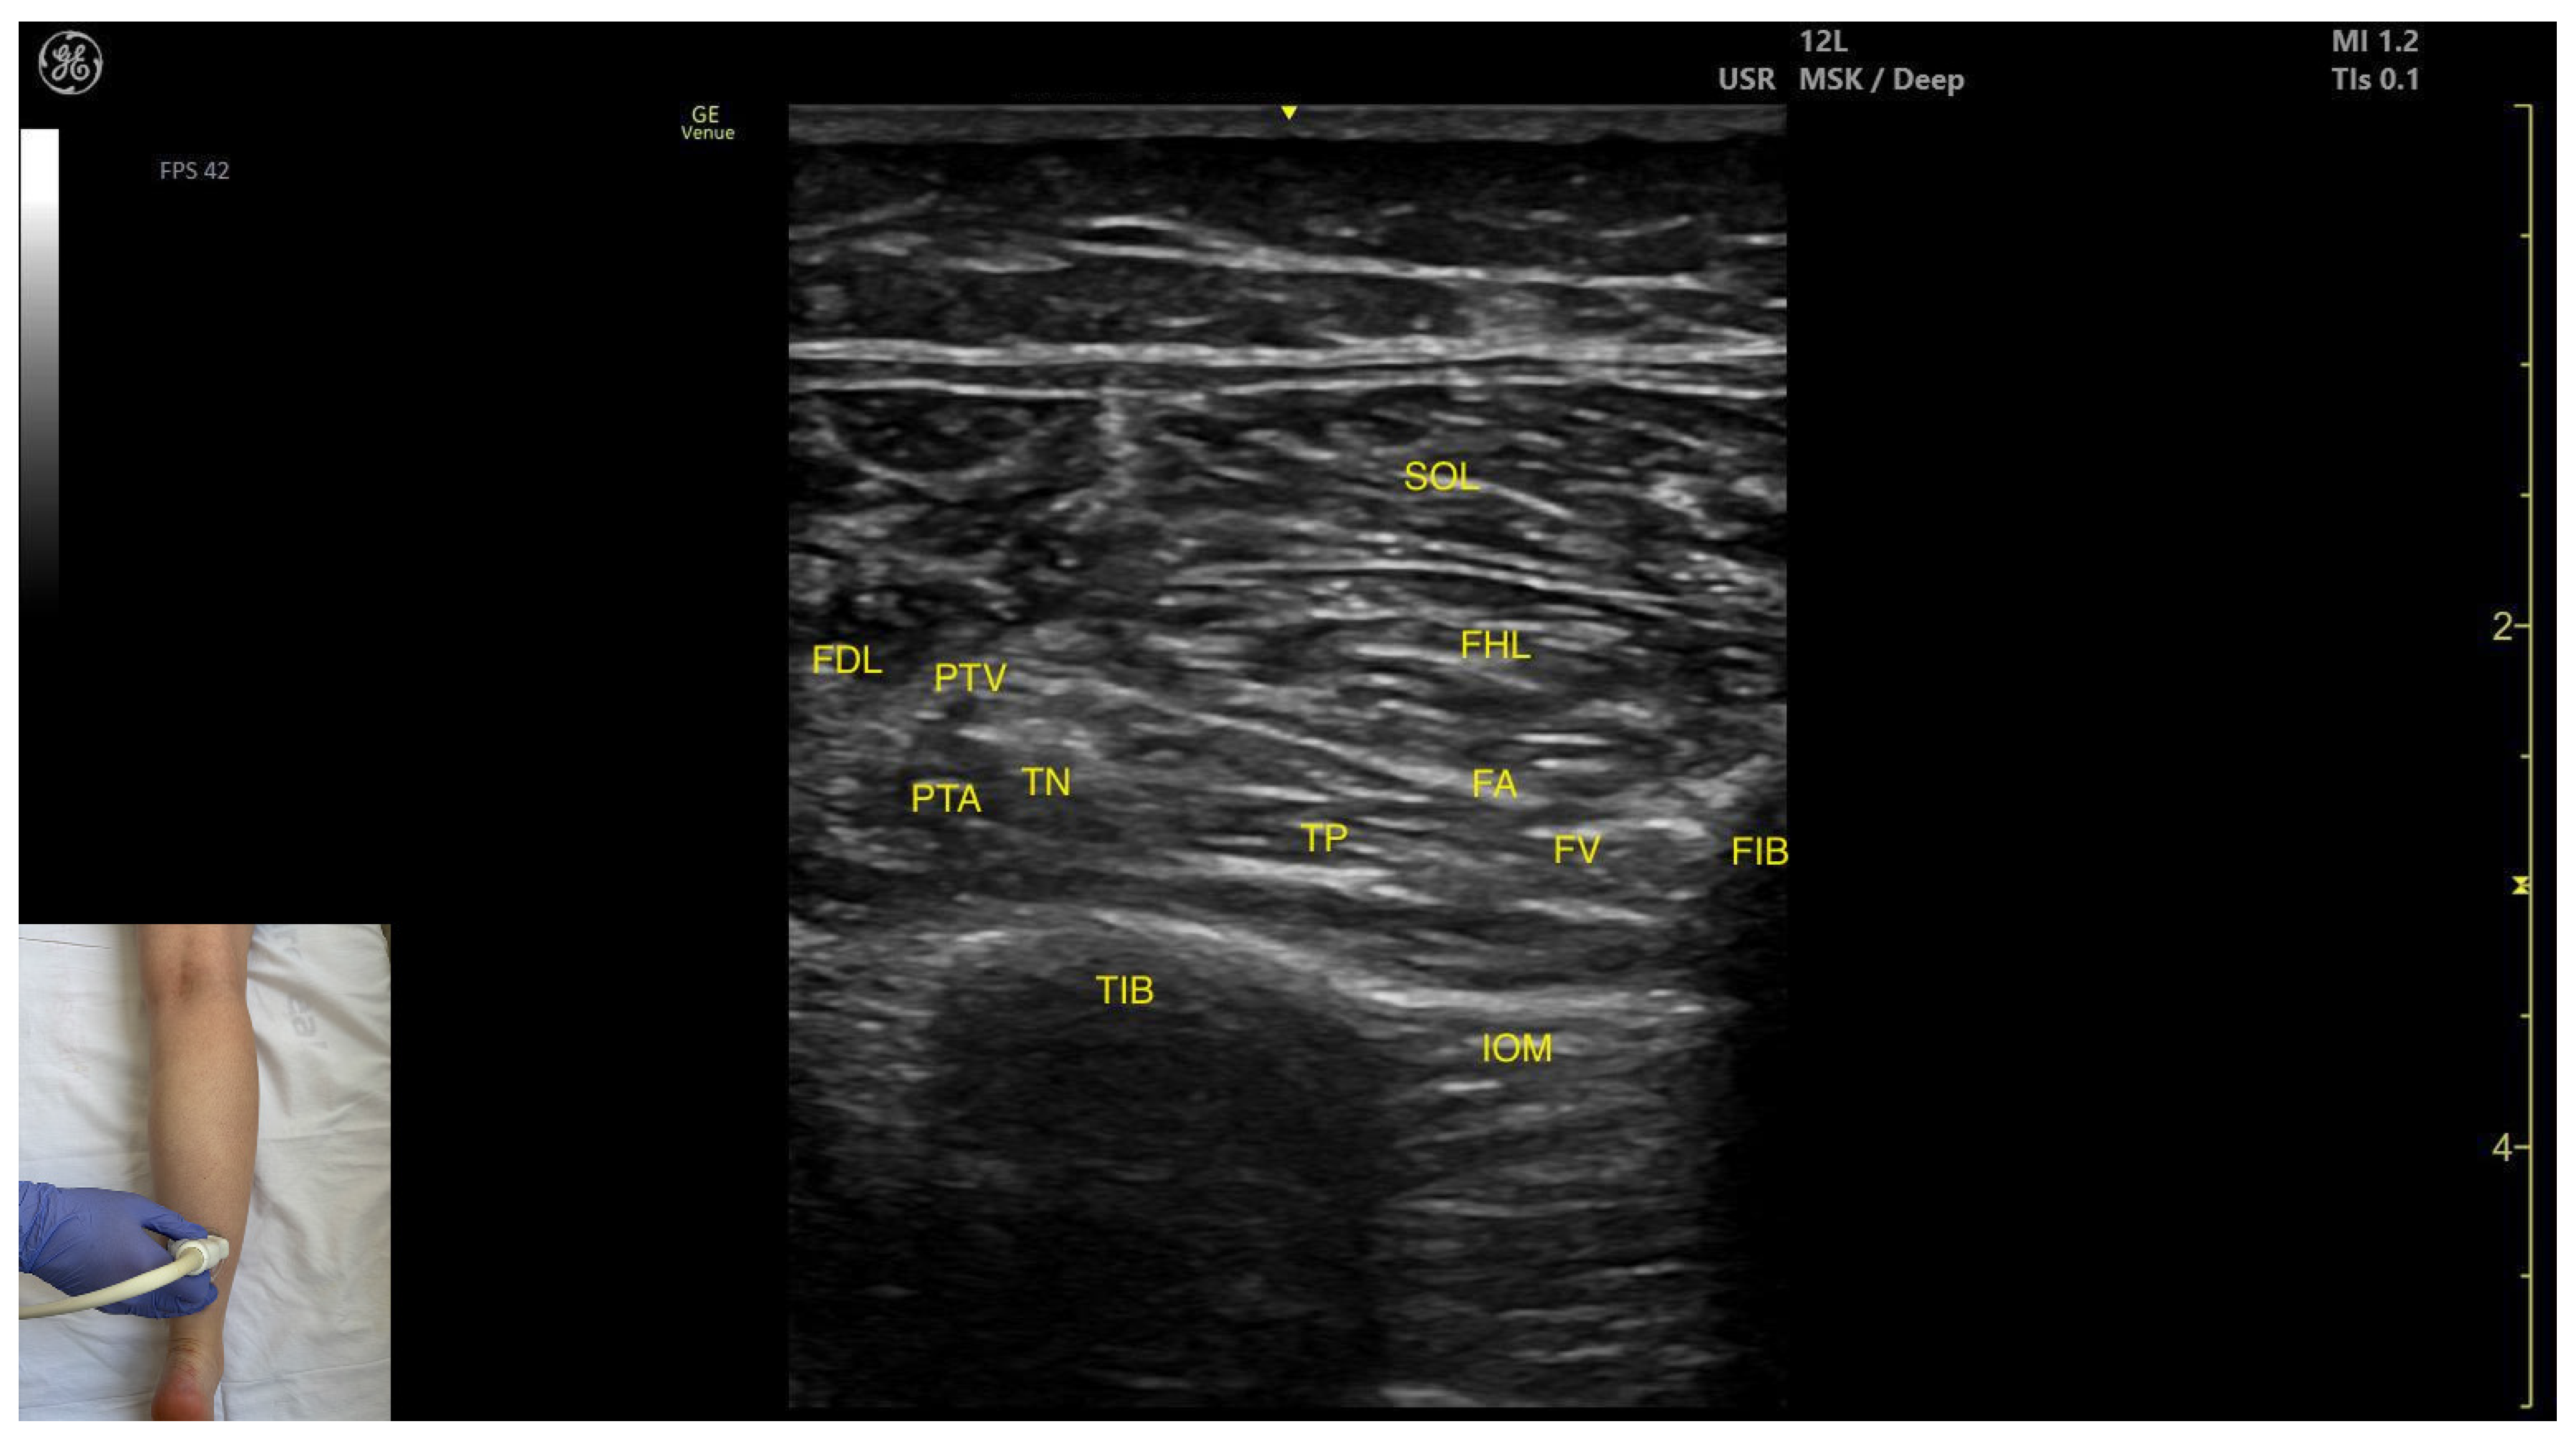

3.3.4. Posterior Window

Ultrasound Identification

Key Ultrasound Landmarks

- Muscle position: The tibialis posterior is the deepest muscle in the posterior compartment of the leg. It is bordered superficially and medially by the flexor digitorum longus, and superficially and laterally by the flexor hallucis longus. The interosseous membrane is located deep to the TP.

- Neurovascular bundle: In the intermuscular fascia between the TP and the FHL run the fibular artery and vein. Additionally, in the intermuscular fascia formed by the soleus, FDL and FHL are the tibial nerve, the posterior tibial artery and the posterior tibial vein.

- External fascia: The TP has pronounced fascia that separates it from the flexor digotorum longus and the flexor hallucis longus, which is relevant for BoNT-A injection.

- Dynamic evaluation: Muscle contraction is visible during ankle inversion and plantar flexion at the ankle joint.

3.4.2. Ultrasound Identification

3.4.3. Key Ultrasound Landmarks

- Muscle morphology: It is a strong, unipennate muscle. In our clinical practice it is referred to as the “shark tail”

- Muscle position: It is located superficial to the fibular cortex. The SOL lies superficial to the FHL. Deep and medial to it lies the tibialis posterior (TP) and, deep to TP, the interosseous membrane. Medial to this region is the flexor digitorum longus (FDL). At this level, the usual anatomical relationship of the FHL and FDL is paradoxically reversed.

- Neurovascular bundle: The tibial nerve, posterior tibial artery, and posterior tibial vein lie within the intermuscular fascia between tibialis posterior, SOL, FDL.

- External fascia: The FHL has a well-defined fascia that separates it from soleus, aiding in safe BoNT-A injection. It does not have a pronounced fascia that separates it from the tibialis posterior and flexor digitorum longus.

- Dynamic evaluation: During dynamic evaluation, scanning proximally toward the knee joint, the FHL muscle thickness decreases, and it disappears from view, while the soleus thickens and the lateral head of the gastrocnemius appears superficially (Video S1). Muscle contraction is seen during flexion of the hallux at the metatarsophalangeal and interphalangeal joints, as well as during plantar flexion at the ankle joint.

3.5.2. Ultrasound Identification

3.5.3. Key Ultrasound Landmarks

- Muscle position: It is located in the medial compartment of the posterior leg. Superficially, it is covered by the soleus; lateral to the FDL lies the flexor hallucis longus; deep and lateral to it lie the TP with the interosseous membrane located beneath it. At this level, the flexor digitorum longus and flexor hallucis longus are paradoxically reversed in position relative to their usual anatomical course.

- Neurovascular bundle: Within the intermuscular fascia between the flexor digitorum longus, flexor hallucis longus, and soleus are the tibial nerve, posterior tibial artery, and posterior tibial veins.

- External fascia: The FDL has a well-defined fascia that separates it from the soleus, which is relevant during BoNT-A injection. It does not have a pronounced fascia that separates it from the flexor hallucis longus and tibialis posterior.

- Dynamic evaluation: During dynamic evaluation, scanning proximally toward the knee joint, the flexor digitorum longus decreases in thickness and disappears from view, while the soleus increases in size and the medial head of the gastrocnemius appears superficial to the soleus (Video S2). Muscle contraction is visible during flexion of toes II–V (at metatarsophalangeal, proximal and distal interphalangeal joints) and ankle plantar flexion.

| Tibialis Posterior (posterior window) | Distal third of the posterior leg | Flexor digitorum longus, tibial nerve, posterior tibial artery and posterior tibial vein (superficial and medial); flexor hallucis longus, fibular artery and vein (superficial and lateral); interosseous membrane (deep) | Transverse scan on the distal third of the leg | Avoid neurovascular injury |

| Flexor Hallucis Longus | Distal third of the posterior leg, in the lateral portion | Soleus (superficial); tibialis posterior, flexor digitorum longus (deep and medial); Interosseous membrane (deep) | Transverse scan on the distal third of the posterior leg | Confirm muscle position and relations |

| Flexor Digitorum Longus | Distal third of the posterior leg in the medial portion | Soleus (superficial); flexor hallucis longus, tibial nerve, posterior tibial artery, and posterior tibial veins (lateral); tibialis posterior, interosseous membrane (deep and lateral); | Transverse scan distal third of the posterior leg | Avoid neurovascular injury |